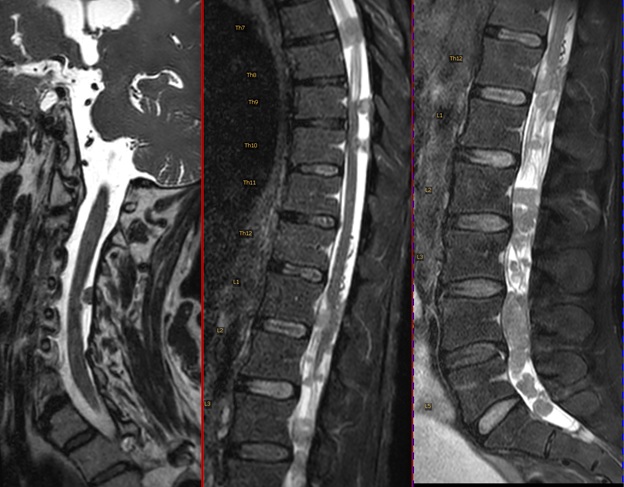

A 59-year-old female with LCNEC presented with progressive neurological symptoms, leading to a comprehensive re-evaluation. Initially, an intracranial cystic-necrotic metastasis in the left frontal lobe was identified (Figure 1), correlating with new-onset aphasia and confusion. Post-surgical analysis confirmed high-proliferation LCNEC, positive for synaptophysin, chromogranin A, CD56, and RB1 wild type. Primary lung involvement was evident in the right upper lobe. Despite cisplatin and etoposide-based radio-chemotherapy, extensive neurocranial and leptomeningeal carcinomatosis (LMC) developed (Figure 2). Whole-brain irradiation (10 x 3Gy) was administered as palliation. By October 2023, the patient experienced right dominant paraparesis, saddle hypesthesia, urinary incontinence, and weakened sphincter function. MRI revealed extensive intradural LMC, compressing the cauda equina at the L4/L5 level (Figure 3). Emergency radiotherapy (Th12-S1, 10 x 3Gy) was initiated, with extended coverage to C1-Th11. Initial improvement was noted; however, the patient's condition progressed to paraplegia.

Figure 3: T2-weighted MRI of the complete spine (cervical, thoracic, and lumbar in sagittal view). Extensive intradural leptomeningeal tumor spread is evident.